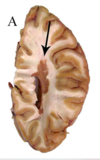

What type of herniation is depicted by the arrow? [1] Uncal Central (transtentorial) Cingulate (Subfalcine) Transcalvarial Upward cerebellar (transtentorial) Downward cerebellar (Tonsillar)

**Uncal** Central (transtentorial) Cingulate (Subfalcine) Transcalvarial Upward cerebellar (transtentorial) Downward cerebellar (Tonsillar)

What type of herniation is depicted? Uncal Central (transtentorial) Cingulate (Subfalcine) Transcalvarial Upward cerebellar (transtentorial) Downward cerebellar (Tonsillar)

What type of herniation is depicted? **Uncal** Central (transtentorial) Cingulate (Subfalcine) Transcalvarial Upward cerebellar (transtentorial) Downward cerebellar (Tonsillar) Uncal herniation. Arrows point to the medial temporal lobe that has herniated through the tentorial incisura to compress the midbrain